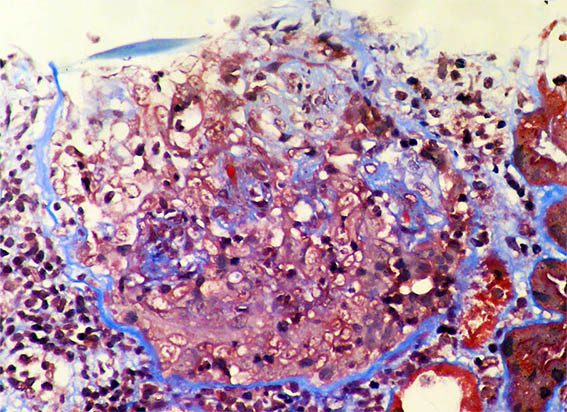

Figura 3.

H&E, X400. Lesión esclerosante segmentaria.

Figura 4. H&E, X400. Otra lesión esclerosante segmentaria.